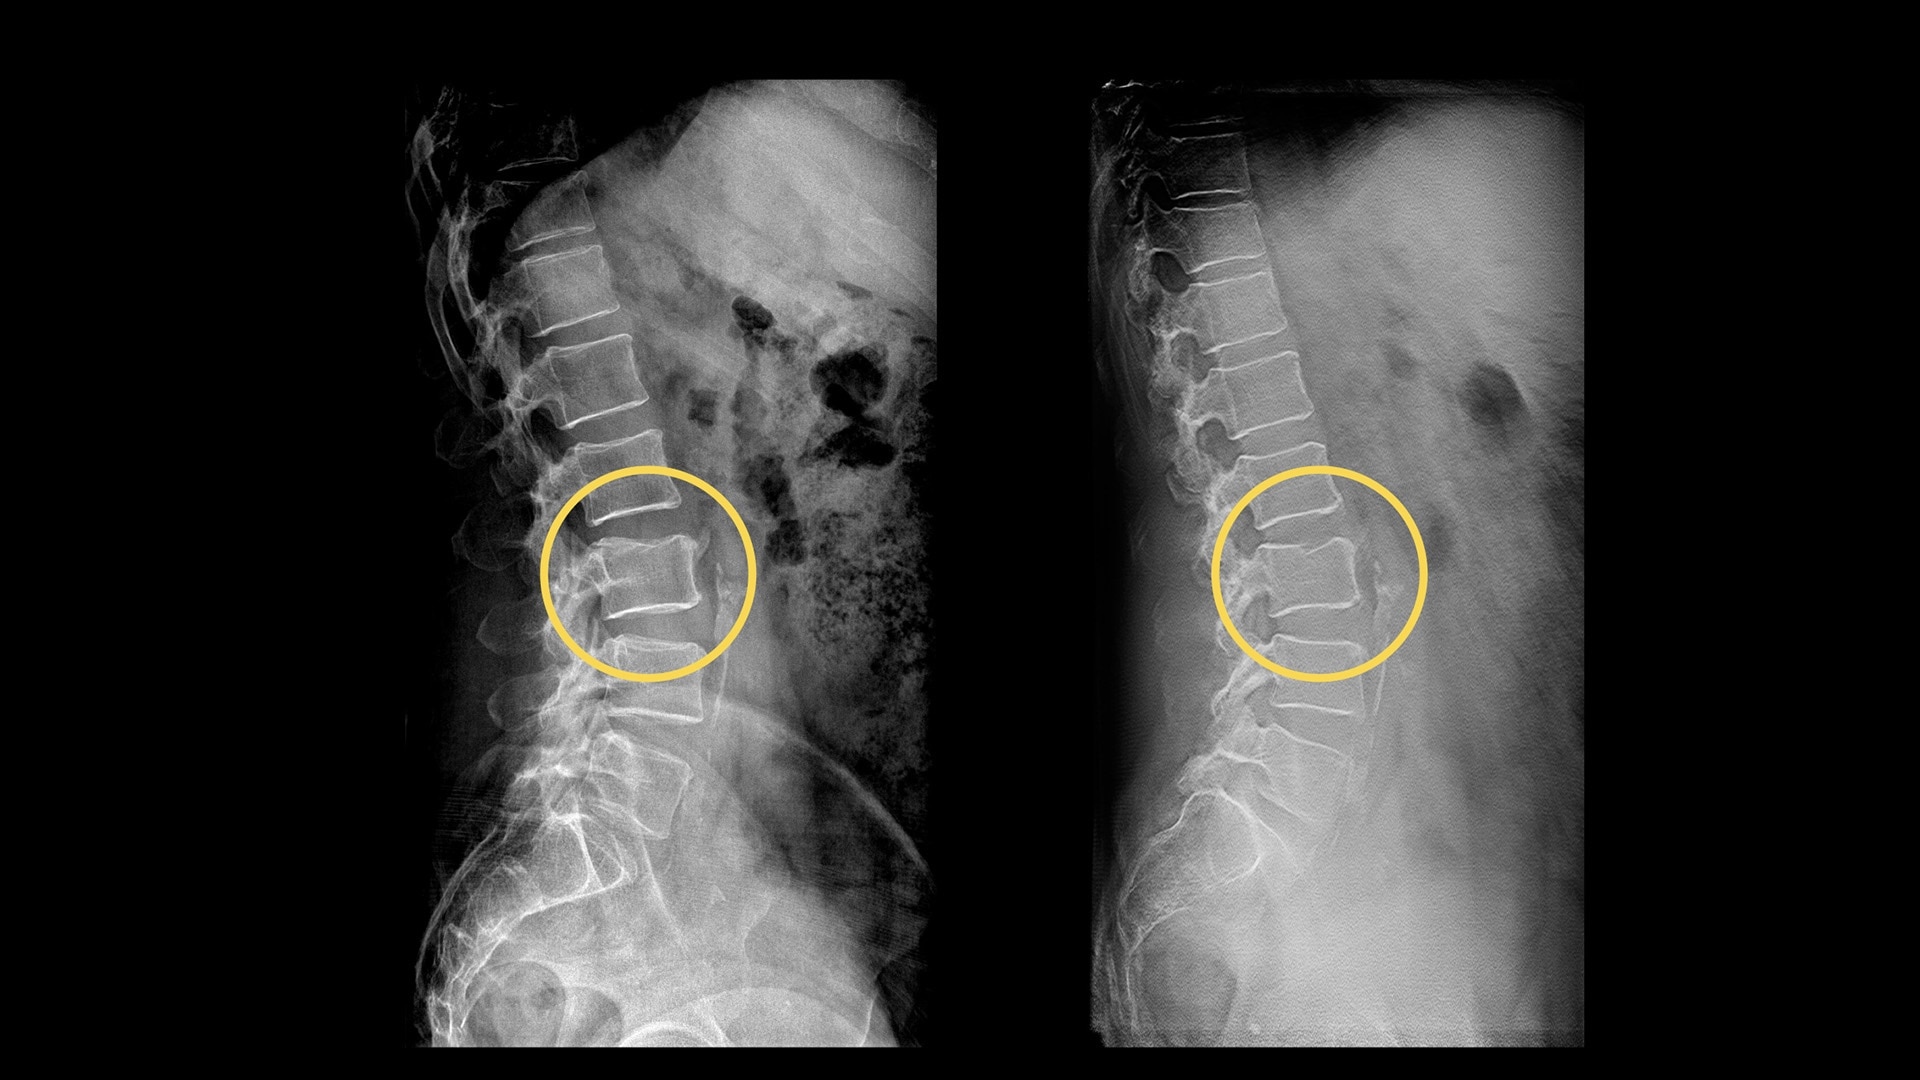

Your department relies on standard radiography as the first diagnostic test for most chest, orthopedic and trauma cases. But hairline fractures or non-displaced fractures are difficult to detect on conventional X-rays.13 According to a recent study, 33% of scaphoid fractures are missed on the first X-ray.14

Digital tomosynthesis can help you reduce time-to-diagnosis, decrease department costs and improve patient outcomes.

• VolumeRAD takes multiple images of the anatomy in a single sweep including chest, abdomen, skull, sinuses, extremities and spine

• Similar to CT exams, the acquired data is then reconstructed into a set of tomographic images (parallel to the detector plane)